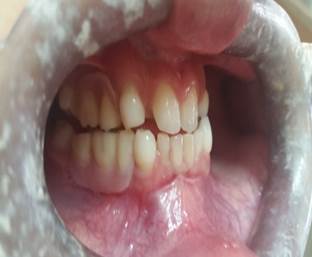

Se inició tratamiento de Ortodoncia, se llevaron hacia mesial para cerrar diastema central entre 11 y 21, con un periodo de contención de dos a tres meses (Figura 3).